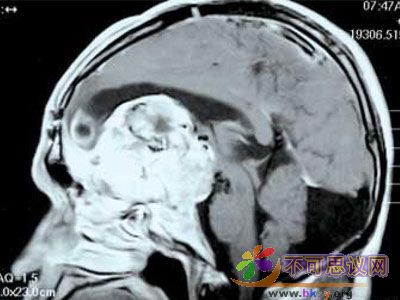

意识的生物学基础是什么?

17世纪的法国哲学家有一句名言:“我思故我在”。可以看出,意识在很长时间里都是哲学讨论的话题。现代科学认为,意识是从大脑中数以亿计的神经元的协作中涌现出来的。但是这仍然太笼统了,具体来说,神经元是如何产生意识的?近年来,科学家已经找到了一些可以对这个最主观和最个人的事物进行客观研究的方法和工具,并且借助大脑损伤的病人,科学家得以一窥意识的奥秘。除了要弄清意识的具体运作方式,科学家还想知道一个更深层次问题的答案:它为什么存在,它是如何起源的。